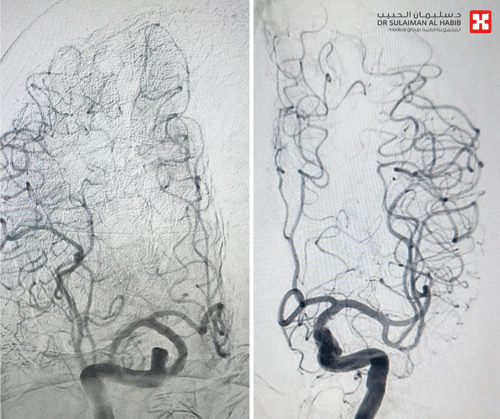

وقالت د. فرح أن المريض وصل للطوارئ مشتكياً من عدة أعراض، أبرزها السقوط المتكرر وعدم القدرة على المشي بسبب الدوار والدوخة، وكذلك الغثيان والقيء والخمول، مشيرة إلى أن الفريق الطبي أجرى له الفحوصات الطبية وأظهرت نتائج التصوير المقطعي المحوسب وجود جلطة في المخيخ، أدت إلى تضيق حاد بالشريان الفقري لذا تم تحويل المريض مباشرة إلى العناية المركزة، ووضع تحت المراقبة، مع بدء إعطائه أدوية السيولة التي ساهمت في فتح الشريان، ومن ثم أجريت له عملية متقدمة باستخدام تقنية الأشعة التداخلية لتركيب دعامة تعمل على إبقاء الشريان مفتوحاً، وتقليل فرص تضيقه مرة أخرى.

واستطردت د. فرح قائلة أن التدخل الطبي الذي استمر «90» دقيقة، مضى حسب الخطة العلاجية، وتكللت جهود الفريق الطبي بالنجاح التام ولله الحمد. وبقي المريض في المستشفى قيد الرعاية الطبية لنحو «48» ساعة، ثم غادر إلى منزله وهو بحالة صحية جيدة، وأظهرت فحوصات ما بعد العملية نجاح التدخل الطبي، كما أن المريض استرد قدرته على المشي بتوازن، وتخلص من الدوار وغيره من الأعراض وعاد لممارسة حياته بصورة طبيعية.